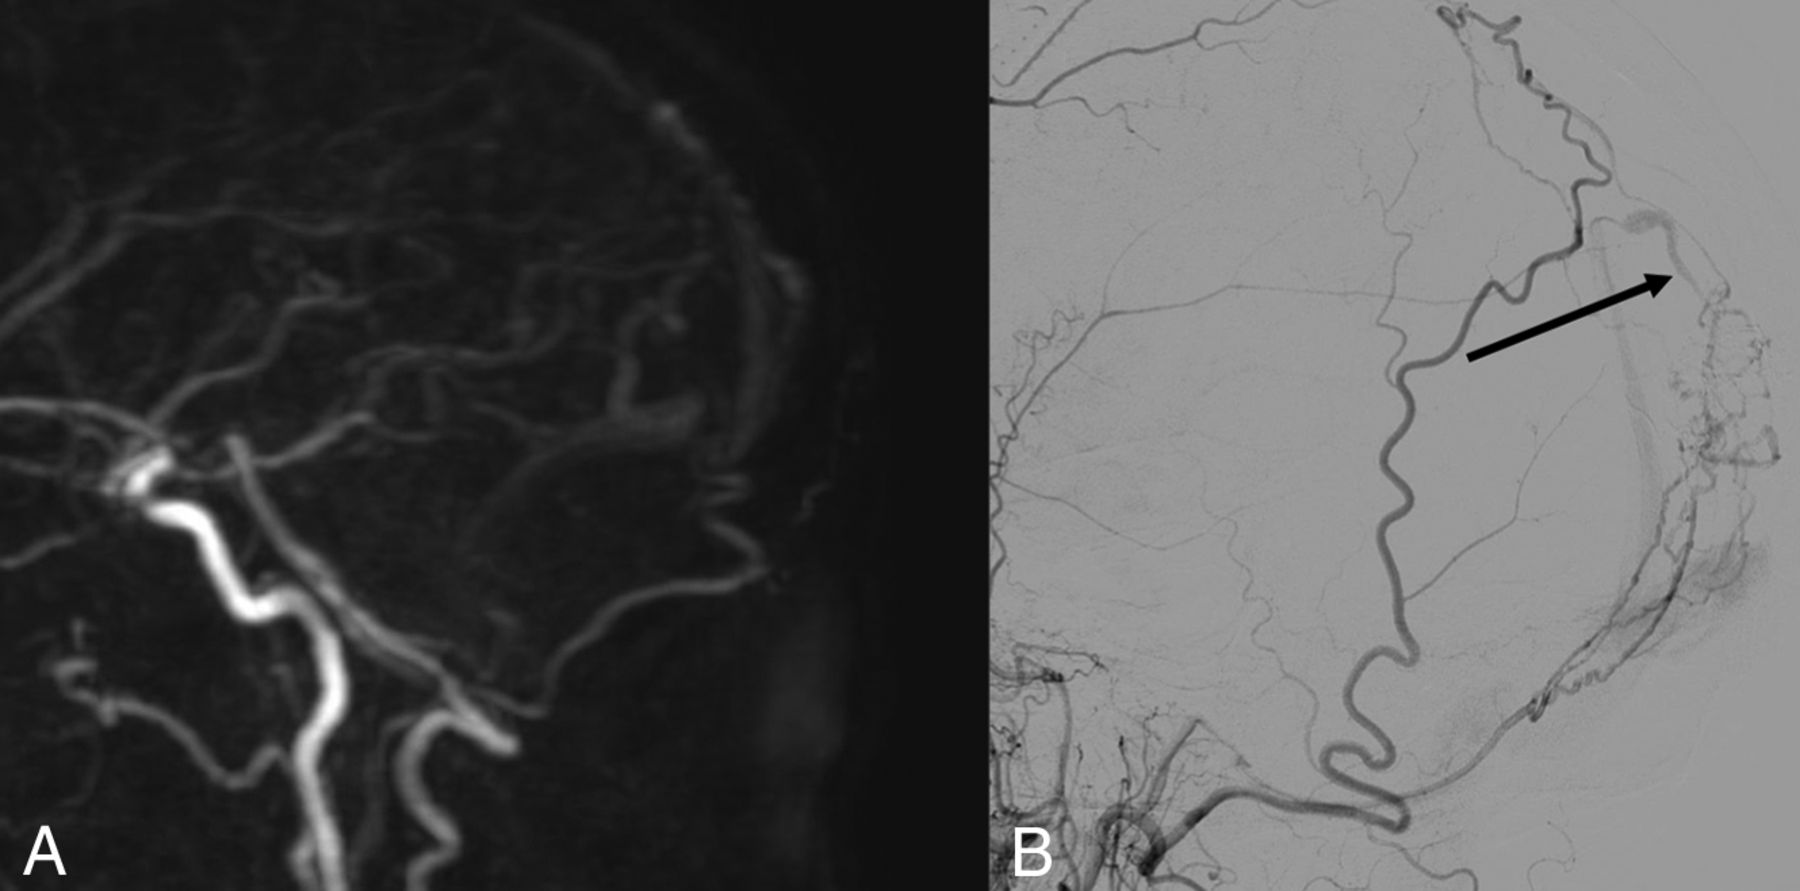

A, Sagittal MIP of 4D-MRA at arterial phase. B, Cerebral arteriography through the left vertebral artery in a sagittal view. The white arrow in A and the black arrow in B show early opacification of an epiphyseal vein, before the superior sagittal sinus, confirming an arteriovenous shunt. This examination was rated type III on both imaging modalities.